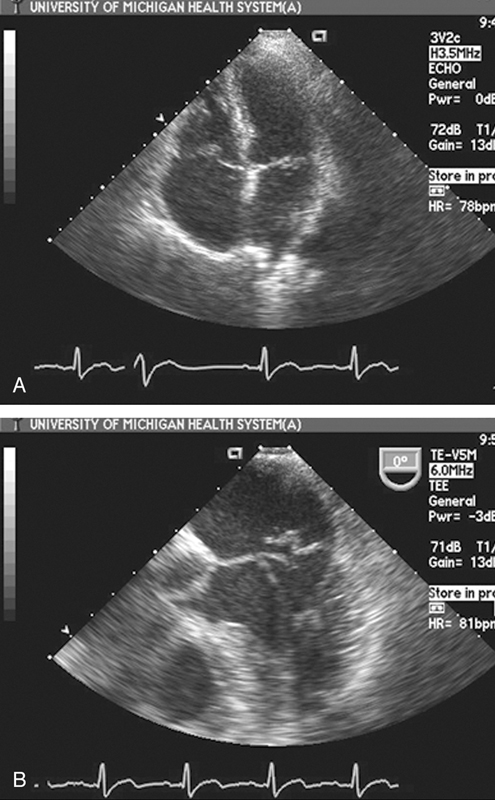

فحوصات تشخيصية لبعض امراض القلب والشرايين التاجية